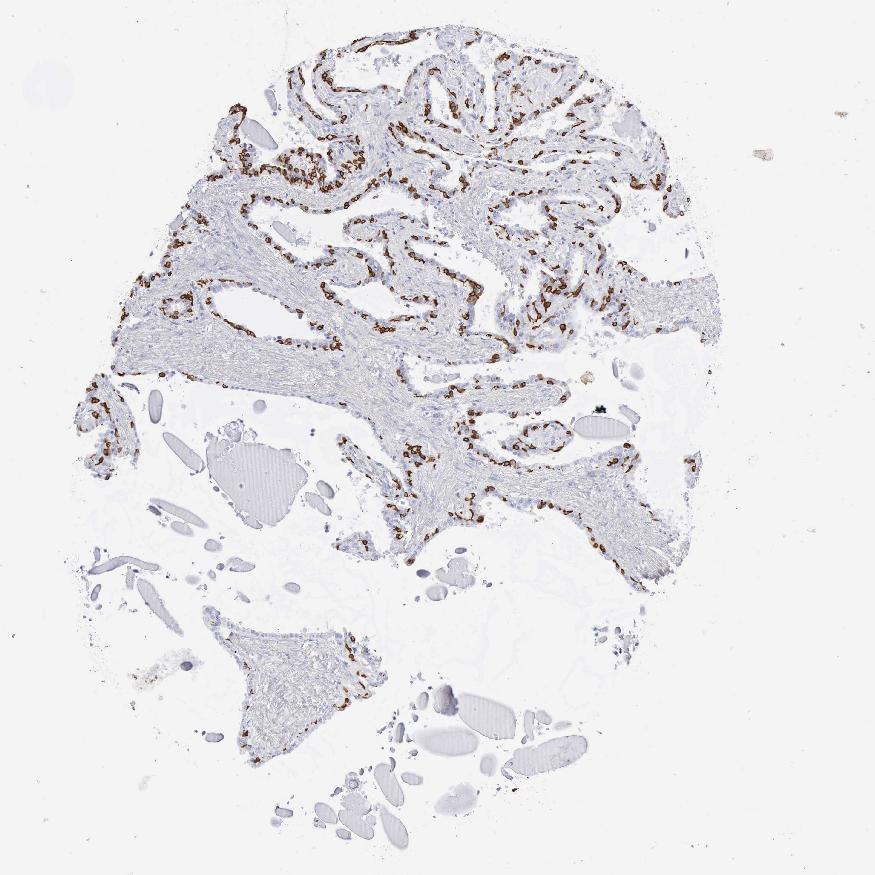

TISSUE PRIMARY DATA SEMINAL VESICLE Show tissue menu

Seminal vesicle

SEMINAL VESICLE - Antibody stainingi

Antibody staining in the annotated cell types in the current human tissue is reported as not detected, low, medium, or high, based on conventional immunohistochemistry profiling in selected tissues. This score is based on the combination of the staining intensity and fraction of stained cells.

Each image is clickable and will lead to virtual microscopy that enables deeper exploration of all samples and also displays staining intensity scores, fraction scores and subcellular localization as well as patient and tissue information for each sample.

Antibody HPA059479Antibody CAB000027Antibody CAB000129Antibody CAB080101

Glandular cells HighHighHighHigh